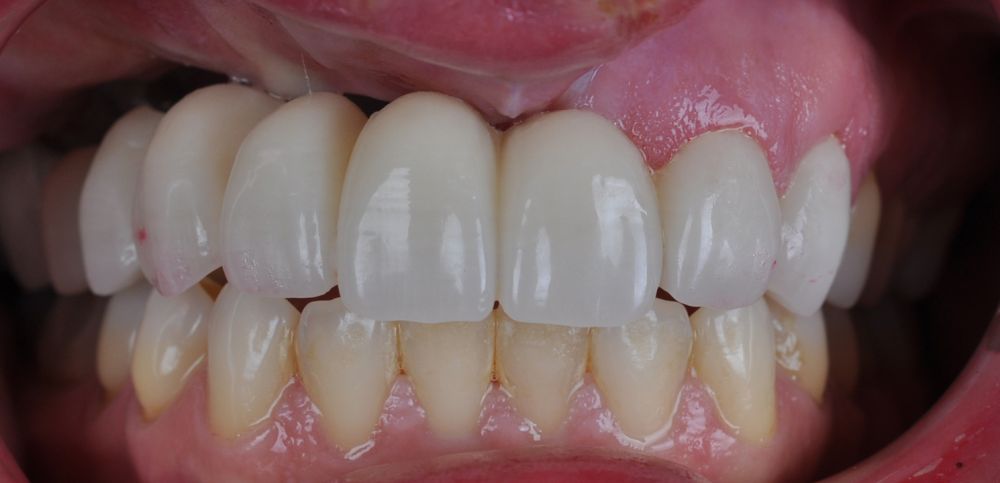

Para la fabricación de las estructuras, se eligió el óxido de zirconio monolítico como material restaurador sobre interfases metálicas en el puente implantosoportado, y coronas de óxido de zirconio monolítico en los dientes tallados previamente (1.7, 1.6, 2.2 y 2.3). Se tomaron impresiones de cubeta abierta con silicona de adición pesada y fluida (Zhermack Elite HD, Gmbh). Se realizó una prueba de pasividad analógica y el resto del proceso se confeccionó de manera digital, por lo que se hicieron pruebas estéticas de dientes impresas en 3D sobre interfases metálicas, para hacer todos los ajustes de función y estética previos al fresado del zirconio monolítico (Figuras 11, 12 y 13).

El día de la colocación de las estructuras, se arenó el interior de las coronas dentosoportadas con óxido de aluminio de 50 m y fueron cementadas con cemento de resina Multilink Ò. El puente implantosoportado se atornilló al torque indicado (20Nw) (Figuras 14, 15, 16 y 17).

Las impresiones analógicas y el posterior flujo digital permitieron una correcta planificación protésica. Las estructuras definitivas, confeccionadas en óxido de zirconio monolítico sobre interfases metálicas de titanio, mostraron una adecuada adaptación pasiva tanto clínica como radiográficamente. La prueba estética permitió ajustes oclusales y funcionales mínimos, optimizando el resultado final.

En enero de 2021, el puente implantosoportado fue atornillado con un torque controlado (20 Nw), y las coronas dentosoportadas cementadas con éxito. La paciente refirió una notable mejoría en la función masticatoria, fonación y estética facial, manifestando un alto grado de satisfacción.